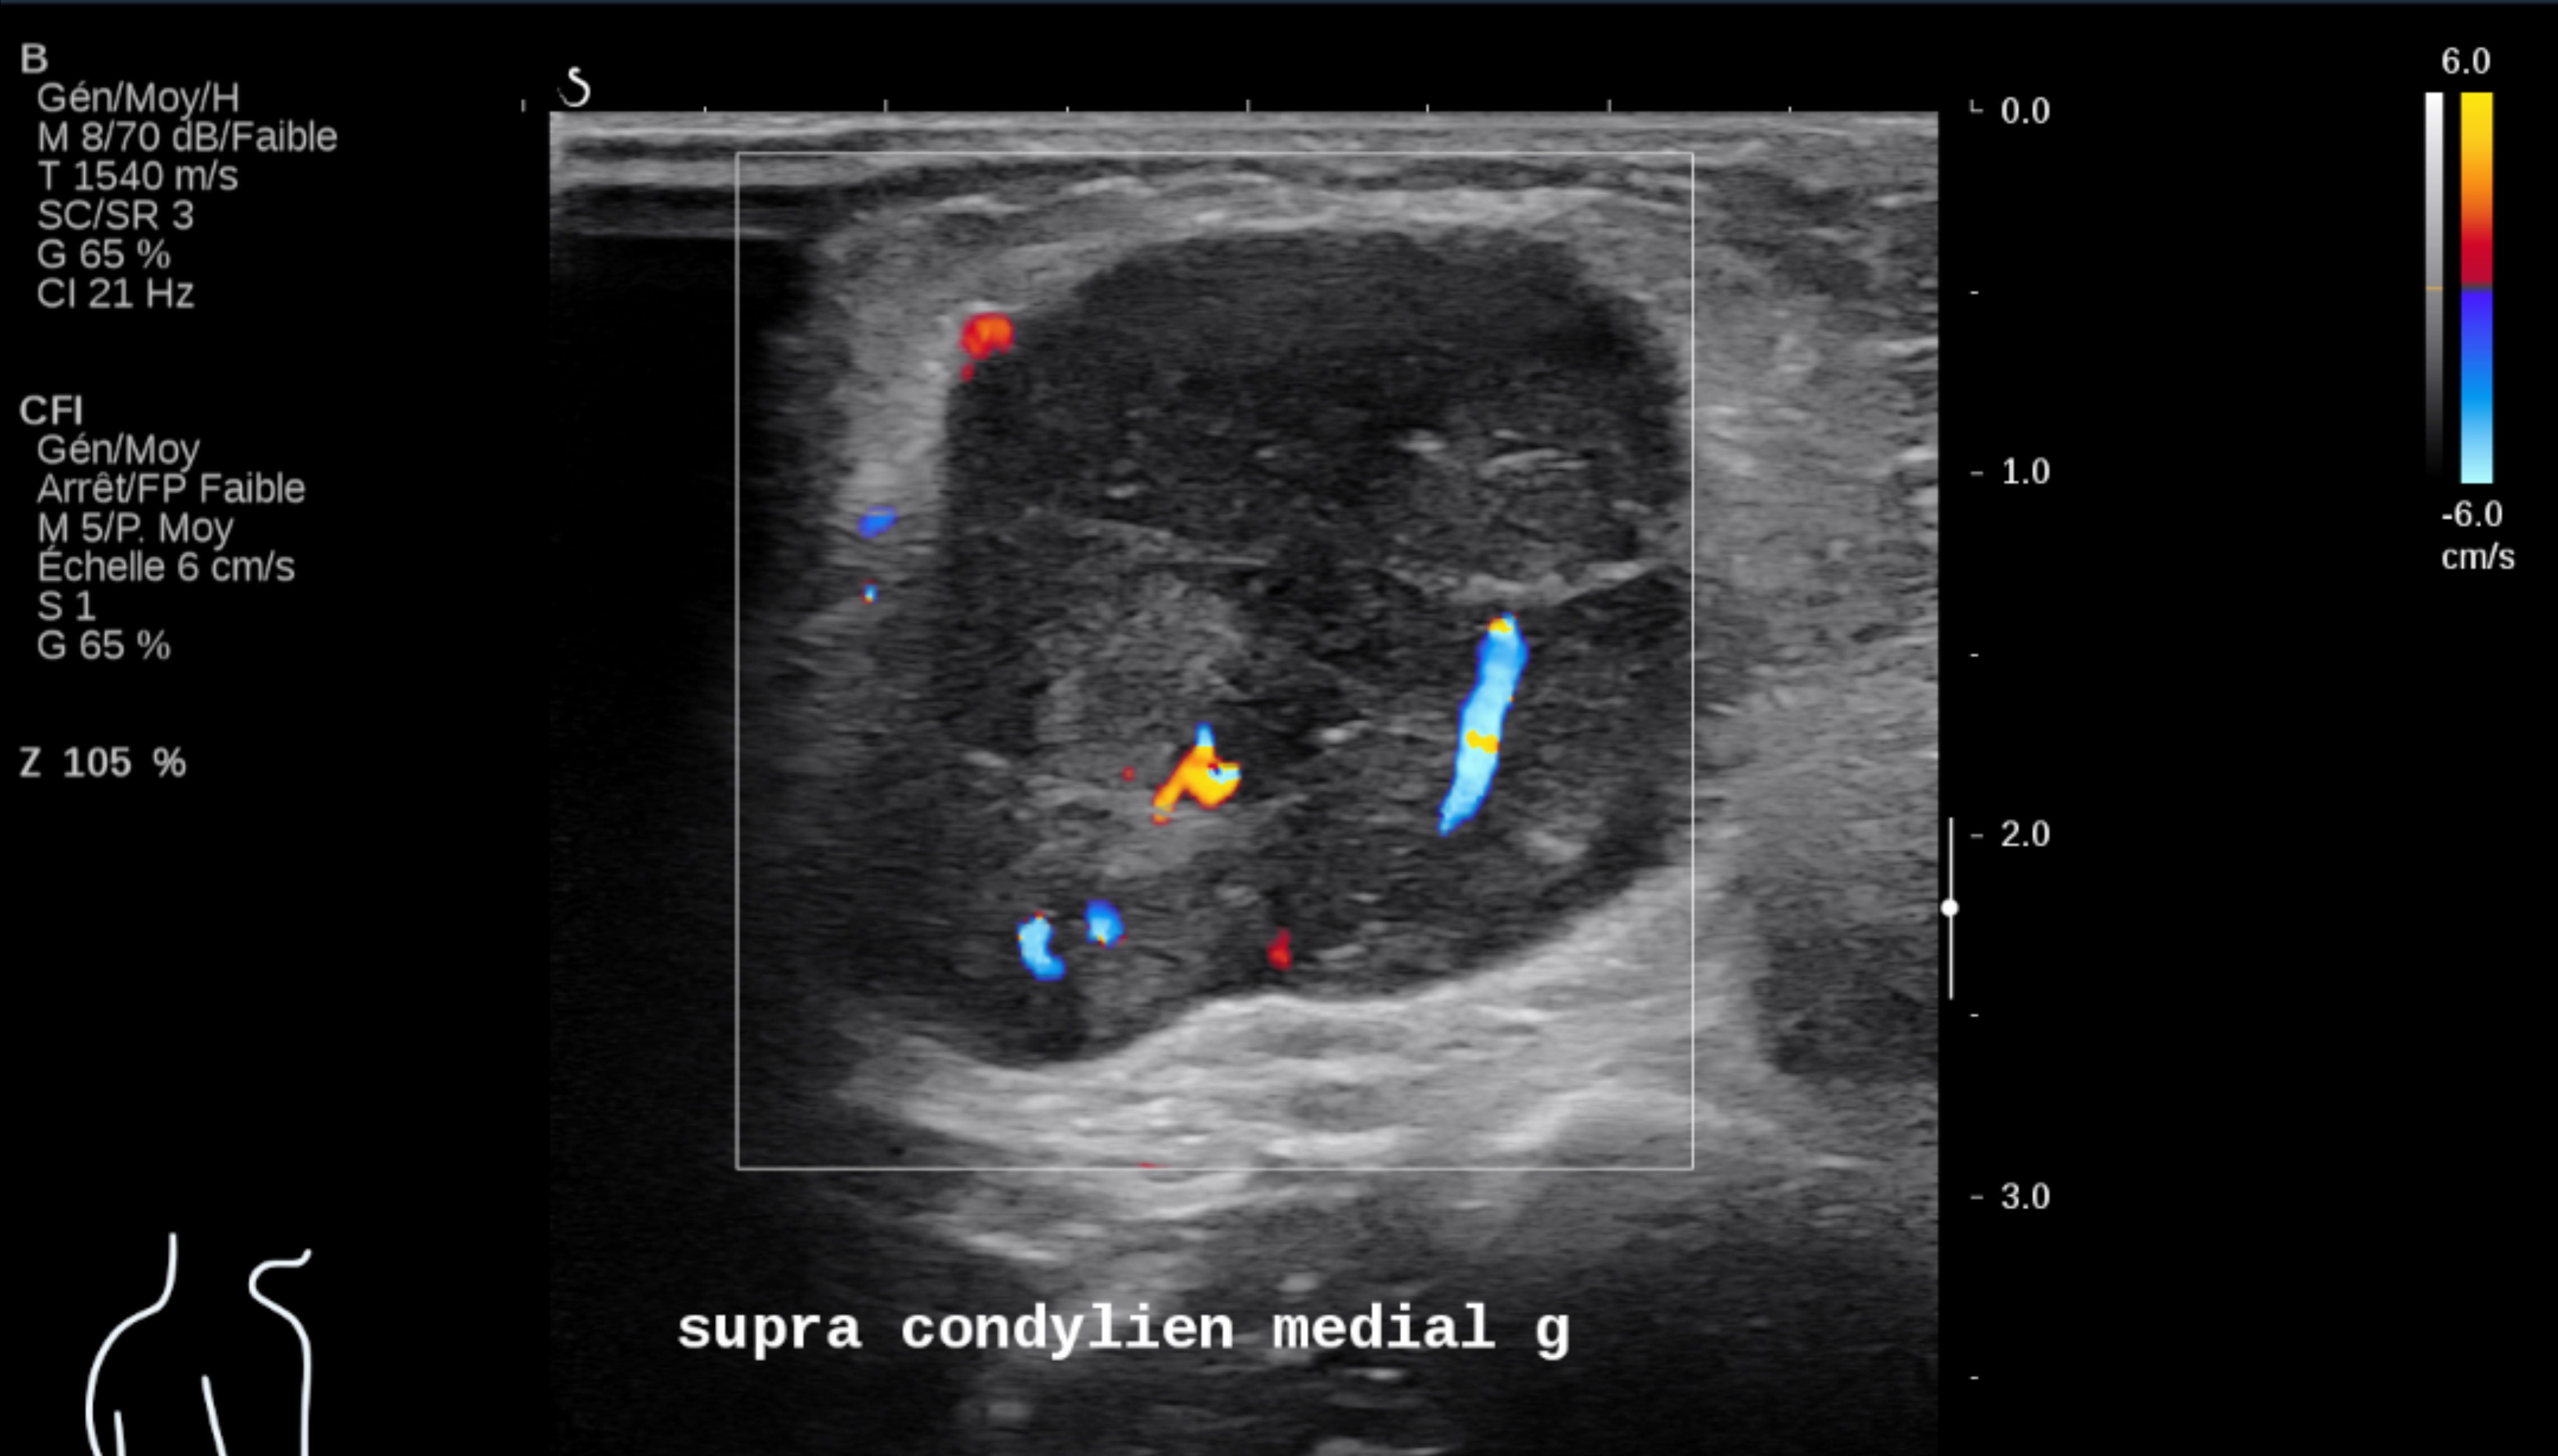

L’échographie reste le meilleur examen pour le suivi ganglionnaire superficiel et cutané des patients, à condition d’être réalisée par des opérateurs entraînés et spécialisés avec des appareils d’échographie performants utilisant des sondes de haute et très haute fréquence.